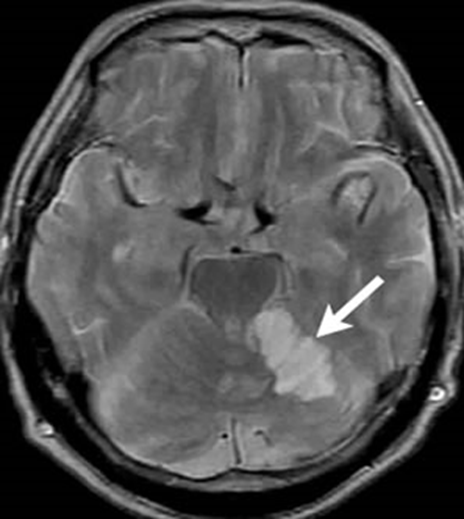

外来に70歳台の女性が家族に連れられてやってきた。9月初めから「ふらつき」「まっすぐに歩けない」「めまい」の症状が出たという。いまはめまいはなくなったが、ふらつきはあるという。しっかりお話もできてマヒなどの神経症状はない。家族は「症状がでてからすぐに外来にきて頭のCTを撮影したが、なんともないと言われた」という。今日は「その後に撮影したMRIの結果を聞きにきた」という。MRIの拡散強調画像をみると立派な小脳梗塞だ。

CTは初期の梗塞を見つけるのは苦手だ。出血だとすぐに黒っぽい影がでるので、分かるけれど、梗塞は分からない。一方、梗塞では少し時間をおいてMRIを撮影すると白くはっきりした画像が現れる。